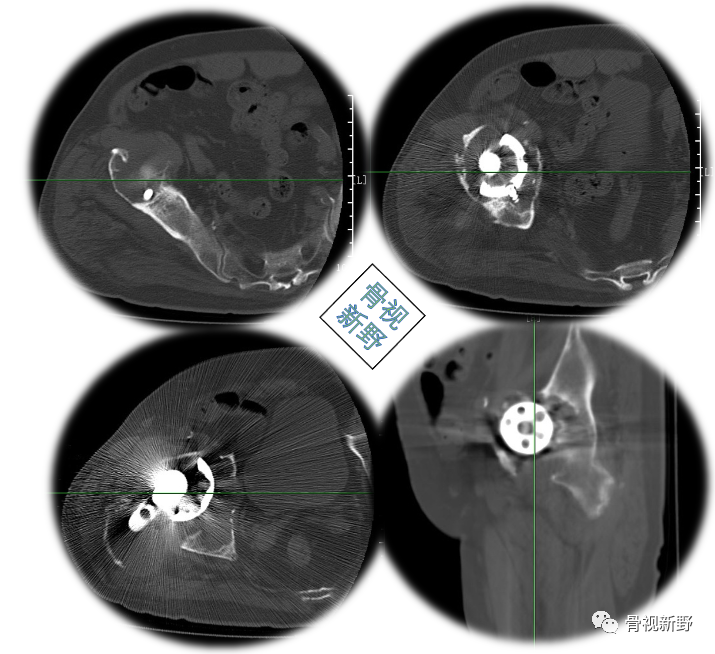

CT提示假体周围骨溶解、骨缺损严重

完善术前常规检查后,择期行翻修术:髋臼侧以cup-in-cup技术翻修;股骨侧以水泥柄翻修。